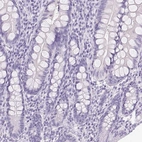

Immunohistochemistry analysis in human kidney and skeletal muscle tissues using HPA064555 antibody. Corresponding ATP6V0A4 RNA-seq data are presented for the same tissues.